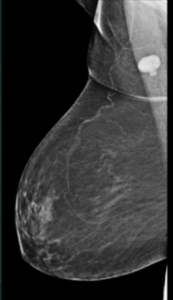

Mammography

Teaching Case 2017